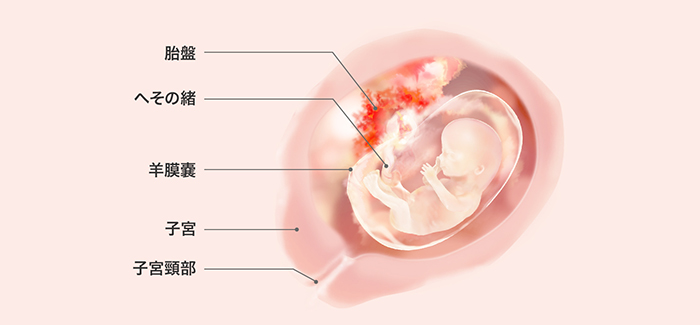

医療監修 妊娠4ヶ月目の妊婦と胎児の様子 健診を待たずに受診すべき症状と生活での注意点 ママリ

妊娠4ヶ月の赤ちゃんの様子 妊娠12 15週 妊娠初期症状 とにかく妊娠チェックをしてみよう

妊娠14週 胎児の様子は 母体の状態は おむつのムーニー 公式 ユニ チャーム

妊娠4ヶ月 胎児の様子や妊婦の症状 妊娠生活注意点 妊娠初期 All About

妊娠14週 胎児の様子は 母体の状態は おむつのムーニー 公式 ユニ チャーム

産婦人科医監修 妊娠14週目 妊娠4カ月 のお腹の赤ちゃんの様子 子育て情報メディア Kidsna キズナ

妊娠14週目は胎児が活発に動き出す時期 妊婦 胎児の様子

妊娠14週 胎児の発育とママの様子をリポート プレママタウン

妊娠14週 たまひよ 医師監修 妊婦の症状や体の変化 赤ちゃんの成長

妊娠14週 エコーで性別がわかる お腹の大きさは こそだてハック

妊娠14週目 赤ちゃんの成長とともに ママのお腹も妊婦らしく変化 胎動はまだ 生理のことから妊娠 出産 育児まで 女性のための情報サイト ルナルナ

妊娠14週 妊娠4カ月 ベビーカレンダー

妊娠4ヶ月 妊娠12週 13週 14週 15週 の胎児と母体の状態 おむつのムーニー 公式 ユニ チャーム

妊娠14週 お腹の張りなど症状やお腹の大きさ 赤ちゃんの成長 エコー写真付き ままのて

助産師監修 妊娠14週目 妊娠4ヶ月 のお腹の中の赤ちゃんの様子について

医師監修 妊娠4ヶ月のママと赤ちゃんの様子 妊娠12週 13週 14週 15週 マイナビウーマン子育て

妊娠14週 胎児と母体の症状で知っておきたいこと ニンアカ

看護師監修 妊娠14週 母体の変化や症状 お腹の大きさ 胎児の様子 Cozre コズレ 子育てマガジン

医療監修 妊娠14週目は胎児が活発に動き出す時期 妊婦 胎児の様子と過ごし方 ママリ